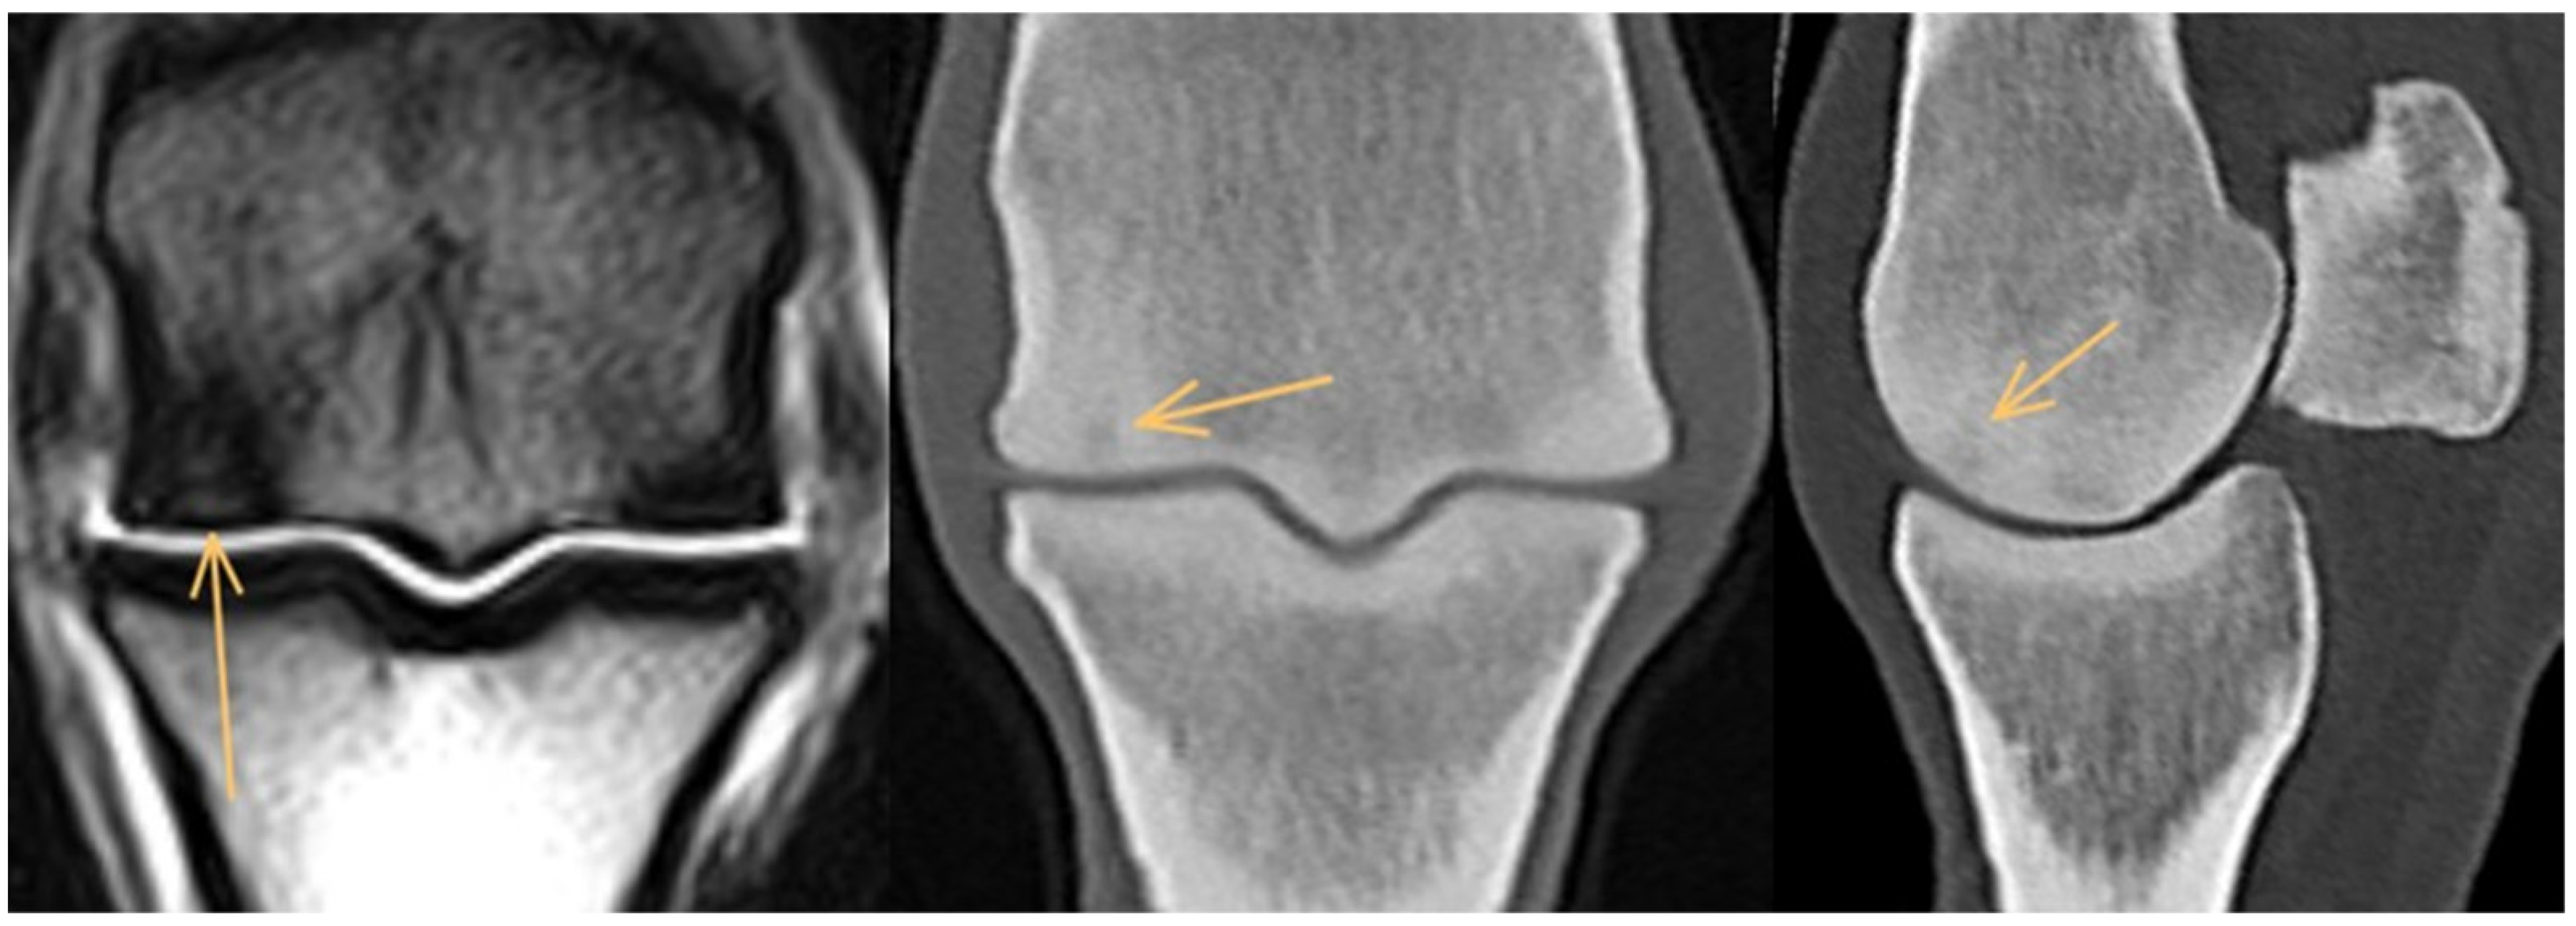

3.1. Third Metacarpal Bone

3.2. Proximal Phalanx